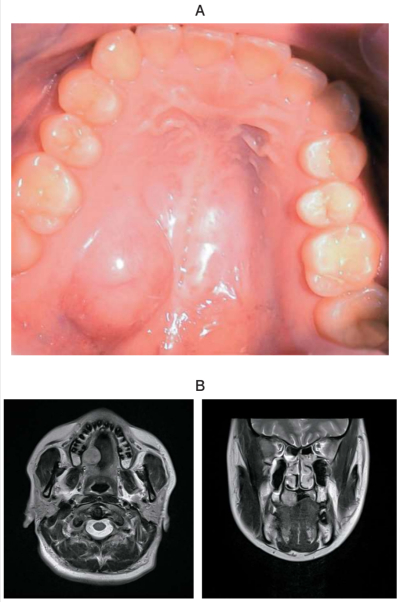

43 歳の女性。口蓋部の腫脹を主訴として来院した。3年前に気付き、その後徐々に大きくなったという。腫脹は弾性硬である。初診時の口腔内写真、MRI T2 強調像及び生検時の H-E染色病理組織像を別に示す。

診断名はどれか。1つ選べ。